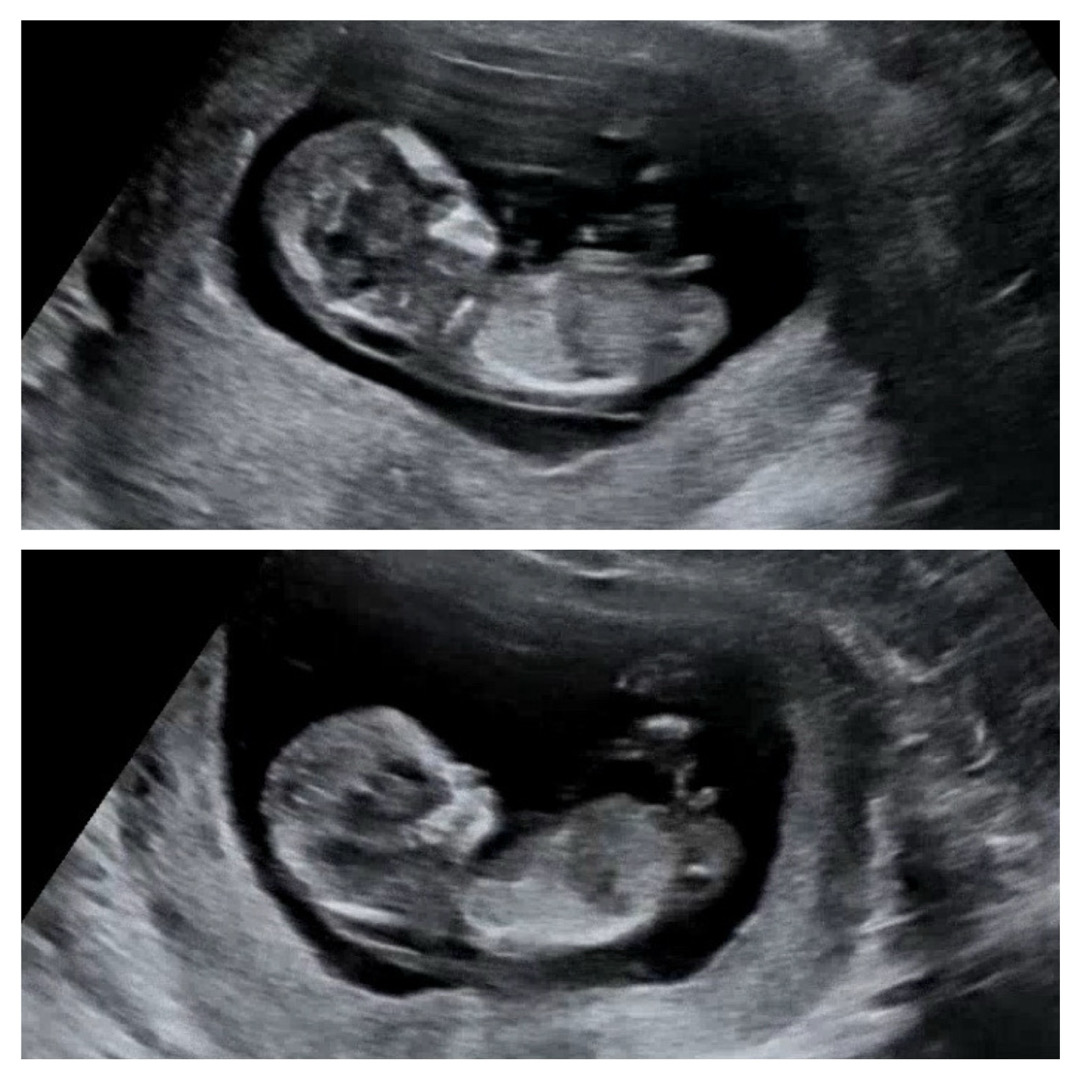

12주 2일 각도법 봐주세요🤍

둘찌라서 성별이 너무 궁금해요,,!🤣 각도법으로 딸일지 아들일지 의견 부탁드려요:)